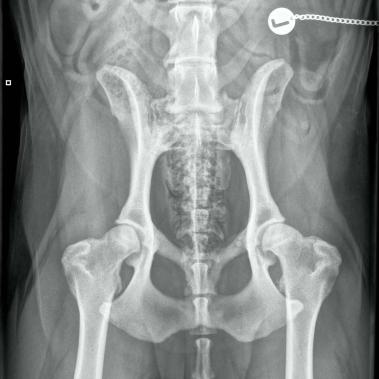

Durch die klinischen Symptome, den Bericht des Besitzers und unter Berücksichtigung des Alters hat Ihr Tierarzt häufig schon einen starken Verdacht. Dieser lässt sich durch die Röntgendiagnostik bestätigen und liefert Hinweise auf den Schweregrad der Erkrankung.

Eine gezielte Röntgenuntersuchung zeigt in der Regel das Ausmass der Arthrose in den betroffenen Gelenken. Leider sind diese Veränderungen nicht heilbar. Das Ziel einer Therapie ist die Verminderung der Schmerzen und die Verbesserung der Gelenkbeweglichkeit.